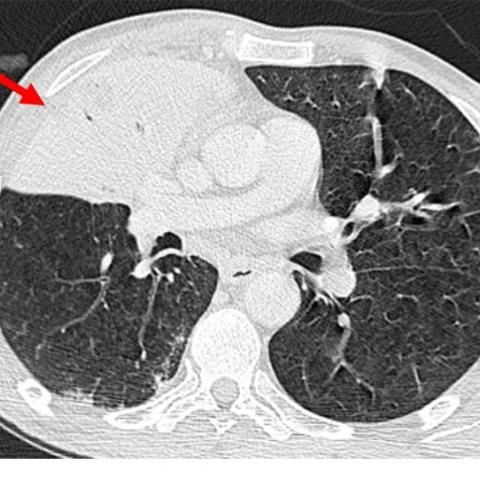

CT显示右上叶和中叶支气管充气征(图2和3)。上叶轻度小叶中心型肺气肿,下叶轻度间隔旁型肺气肿,下叶支气管壁增厚。纵隔淋巴结病变(图3)。无胸腔积液。

图3 右上叶大量实变伴支气管充气征(红色箭头)